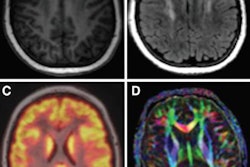

For their review, Spick and colleagues examined PET/MRI versus PET/CT in a wide range of cancer studies, including head and neck, gastrointestinal, gynecologic, and breast cancers, as well as lymphoma and neuroendocrine tumors. The most noteworthy findings were for prostate, bone, and lung cancers.